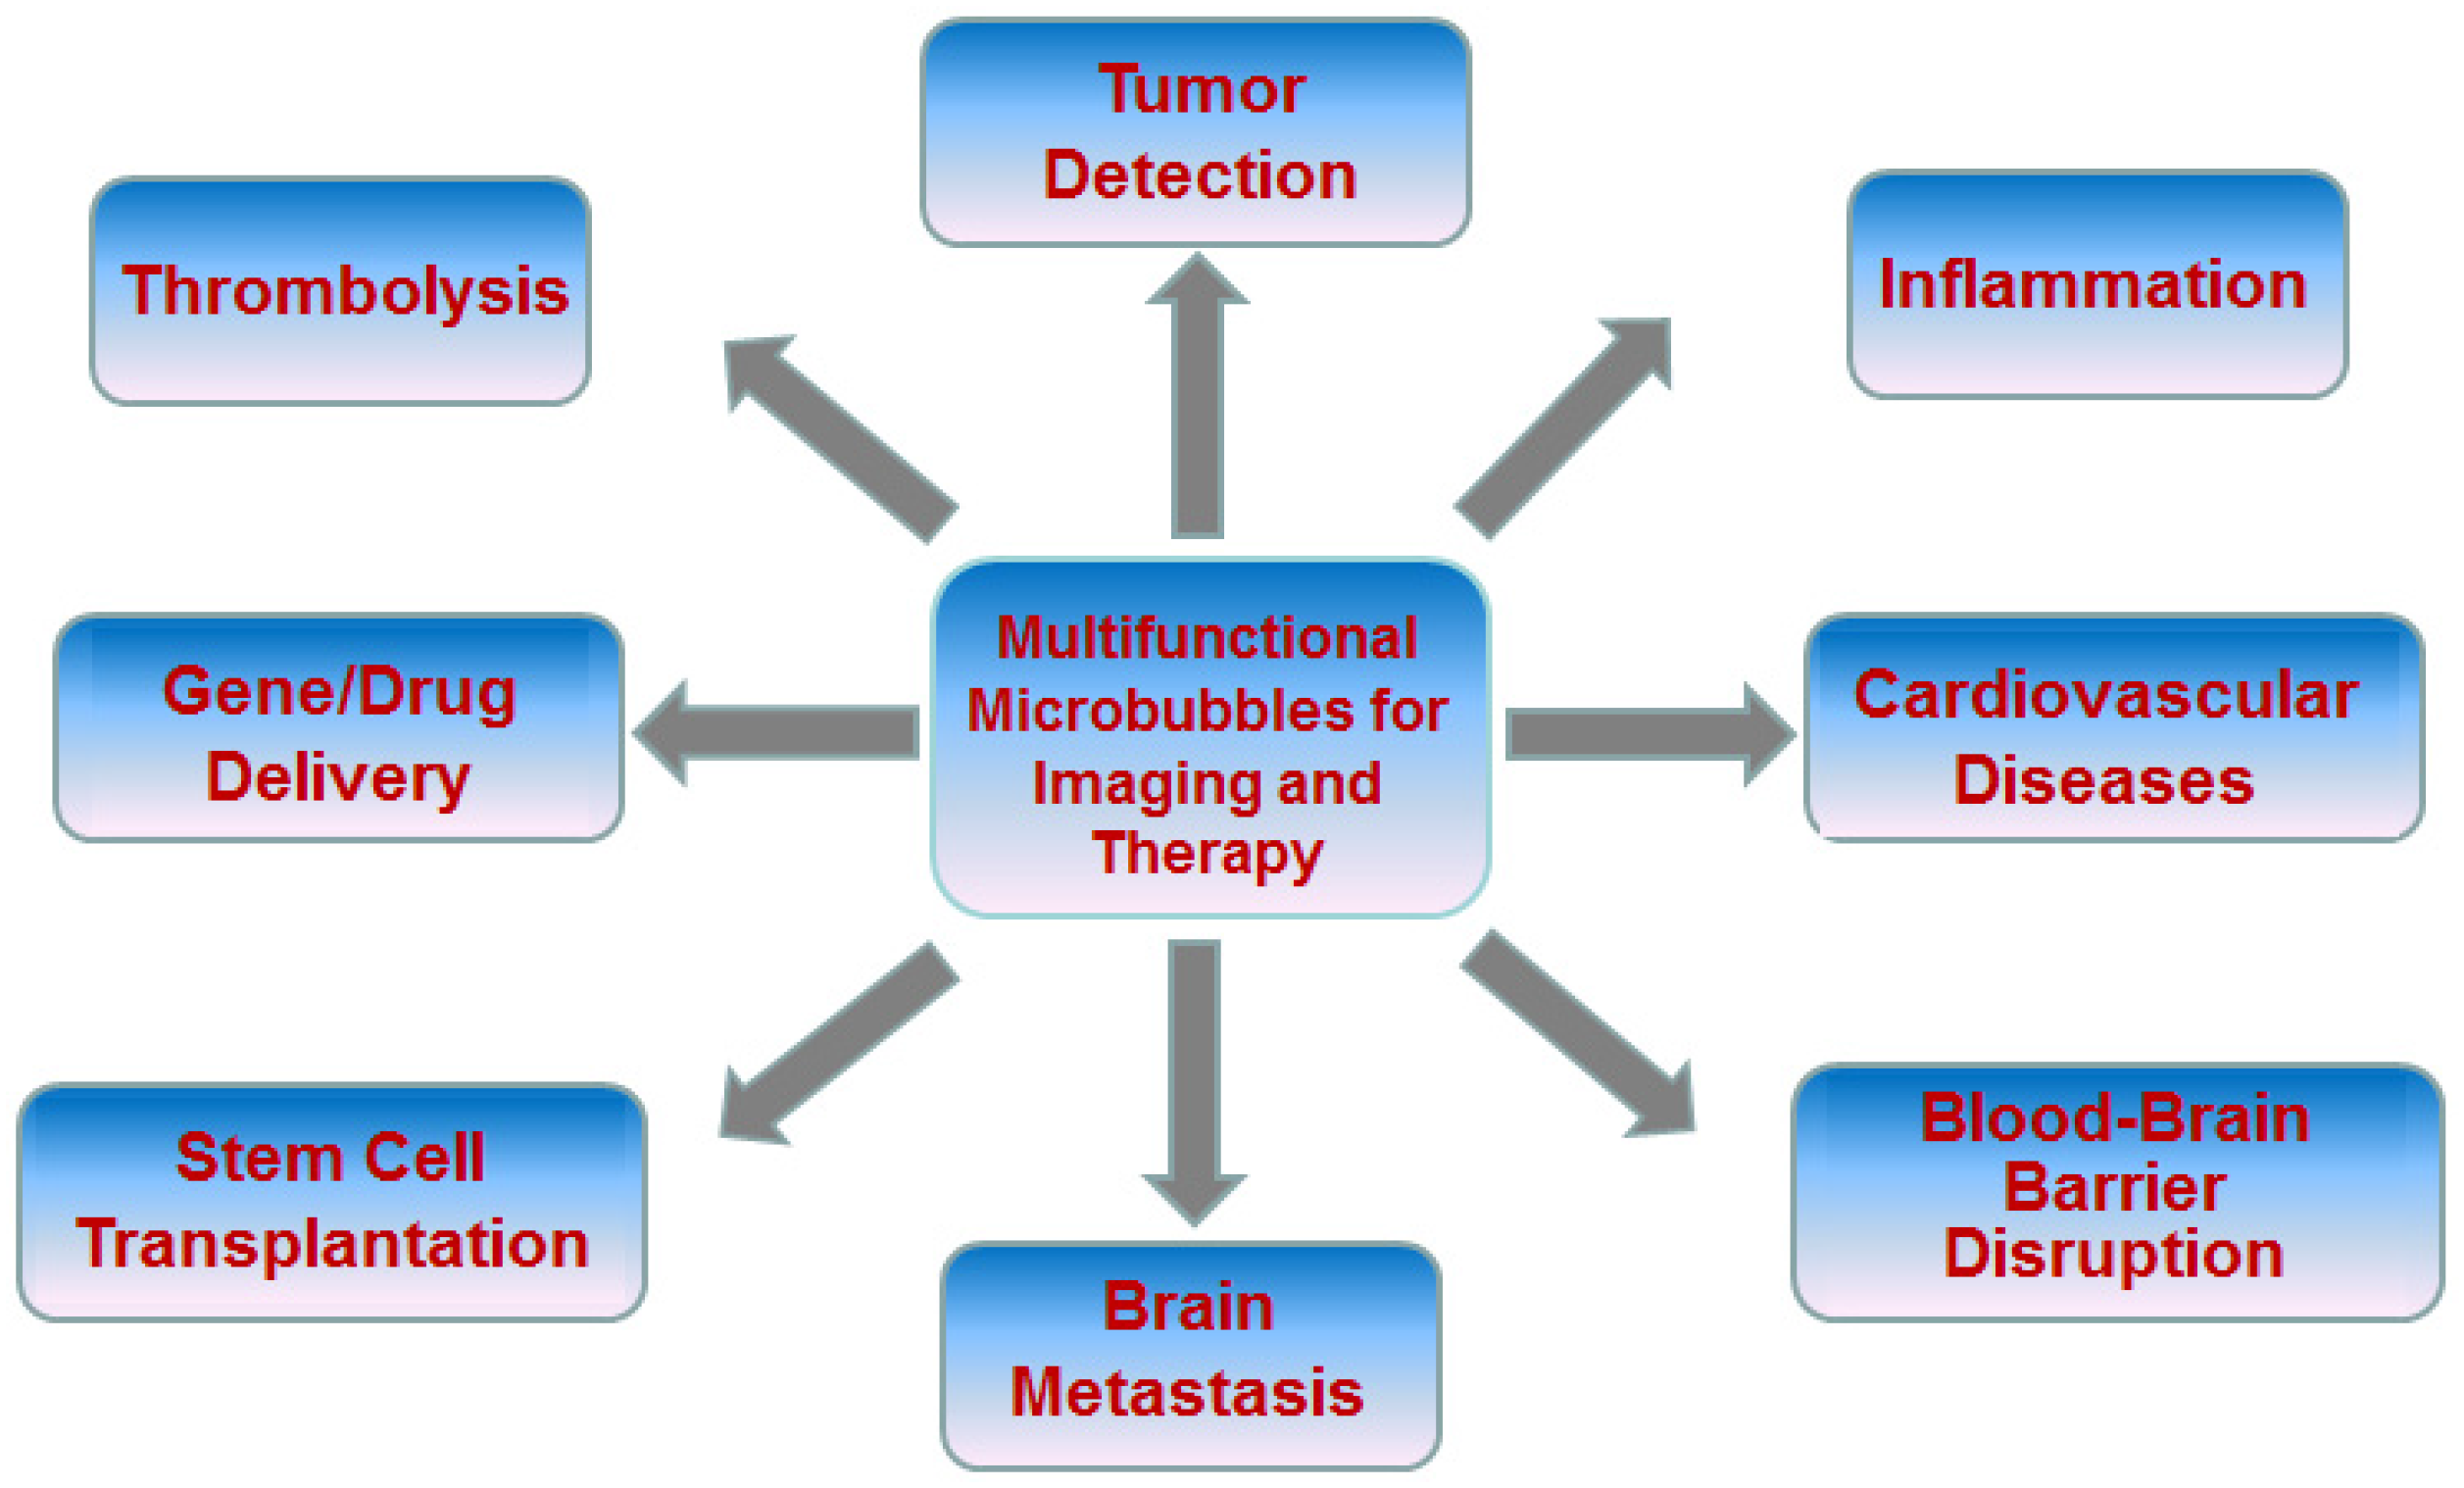

2. Advanced Microbubbles for Imaging and Therapy